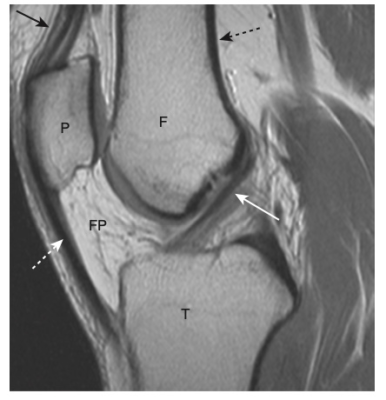

- Chụp cắt lớp vi tính (CT) và chụp cộng hưởng từ (MRI) có thể thấy toàn bộ bao ngoài và chất nền bên trong của xương, bao gồm (đặc biệt là với MRI) các mô mềm xung quanh không thể nhìn thấy trên phim chụp X quang thông thường. (Hình-2).

- Ngoài các bè xương, khoang tủy còn chứa tủy đỏ và tuỷ vàng. Tủy đỏ sản xuất tiền chất của các tế bào máu. Tủy vàng chứa chất béo. Thành phần của tủy là khác nhau đối với các xương khác nhau của cơ thể và thay đổi theo tuổi. Tuổi càng cao tuỷ xương càng ít hoạt động tạo máu, do đó, vào khoảng 30 tuổi, hầu hết bộ xương chi chỉ chứa tủy vàng, trong khi hầu hết tủy đỏ nằm ở xương trục. MRI là một phương tiện tuyệt vời để nghiên cứu các thành phần của tủy, nó rất hữu ích trong việc nghiên cứu bệnh lý tủy xương.

- Trong khi vỏ xương là phần xương dễ nhìn rõ nhất trên phim X quang thông thường, thì vỏ xương lại có cường độ tín hiệu rất thấp trên các lát cắt MRI thông thường.